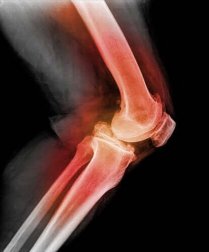

A patela ou rótula é um pequeno osso coberto de cartilagem e de forma triangular. Está localizada na parte da frente do joelho e sobre ele estão inseridos o tendão do quadríceps e o ligamento patelar.

Para o diagnóstico de um deslocamento da rótula o médico apalpará a rótula e dobrará o joelho, movendo-o em direções diferentes. Através do uso de radiografias, ressonância magnética (RM) ou tomografia computadorizada (TC) podem ser vistas imagens de uma rótula deslocada e qualquer outra lesão no joelho. Esses exames são definitivos para detectar esta lesão no joelho.